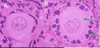

What is labelled A Chlamdyia infection Endometriosis Fibroids Gonorrhea infection Polycysitc ovary syndrome